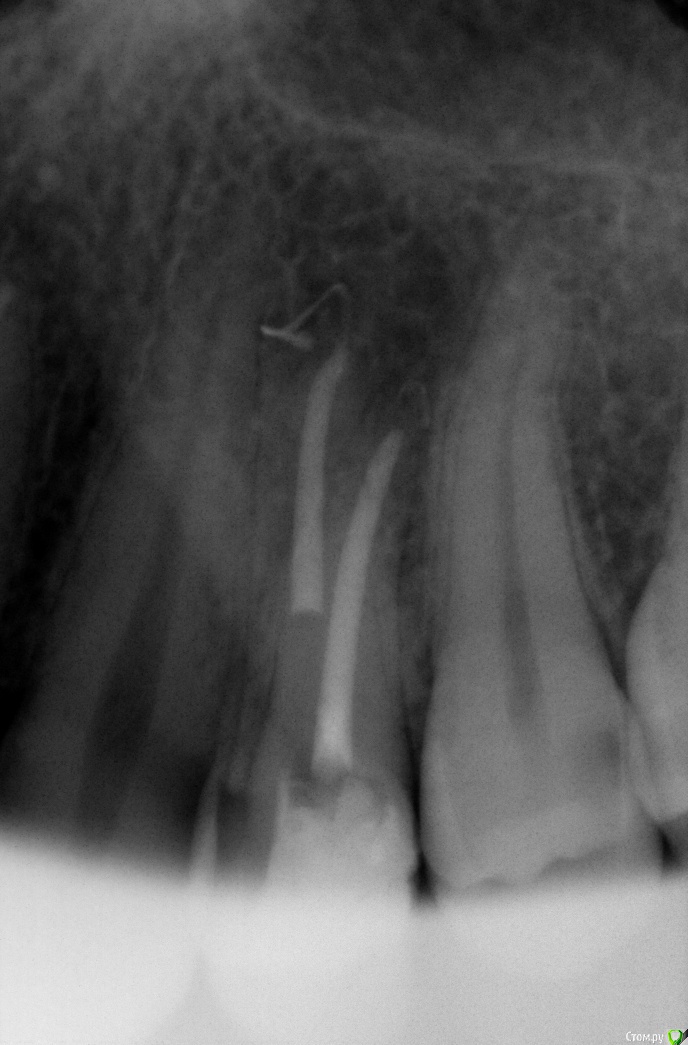

Zemtsov.alexander Опубликовано 28 августа, 2019 Поделиться Опубликовано 28 августа, 2019 Всем доброго времени суток, лечил 46 зуб по поводу пульпита, при вертикальной пломбировки вывел в медально-язычном канале гуттаперчу за верхушку, ваши прогнозы, какой ваш опыт в таких ситуациях? Пациент был неделю спустя, первые 2 дня зуб реагировал при накусывании, сейчас боль почти сошла на нет. Ссылка на комментарий

annda Опубликовано 30 сентября, 2019 Поделиться Опубликовано 30 сентября, 2019 не беспокойтесь, это не главное24_4668.jpg24_7625.jpg24_119616.jpgСилер, нет? Ссылка на комментарий

Гарриевич Опубликовано 3 октября, 2019 Поделиться Опубликовано 3 октября, 2019 Силер, нет?инжектор, гутта точно Ссылка на комментарий